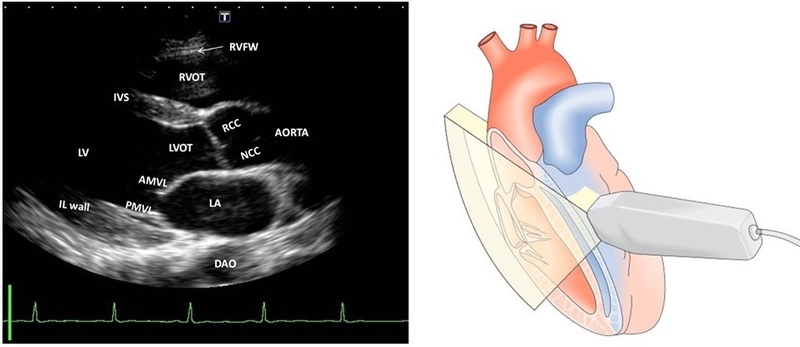

Mặt cắt cạnh ức là mặt cắt được thực hiện ở vị trí cạnh ức, ở phía bên trái của cơ thể. Mặt cắt này giúp bác sĩ quan sát được các cấu trúc sau:

Mặt cắt cạnh ức là mặt cắt quan trọng nhất trong siêu âm tim. Thông qua mặt cắt cạnh ức, bác sĩ có thể đánh giá được chức năng và cấu trúc của thất trái, kích thước các buồng tim, van tim và vách tim, vị trí của tràn dịch màng tim và phân biệt giữa tràn dịch màng tim với tràn dịch màng phổi.